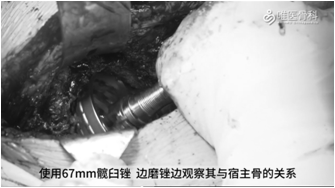

髋臼制备:磨锉髋臼,磨锉过程中要注意保留骨量,过多的磨削会累及髋臼边缘造成节段型缺损。本病例起初用65mm髋臼锉测试稳定性不佳,然后使用67mm髋臼锉,边磨锉边观察其与宿主骨的关系,然后进行反锉压实。测试髋臼锉稳定性好,如果仍怀疑其稳定性,可使用髋臼假体试模再次评估其稳定性。